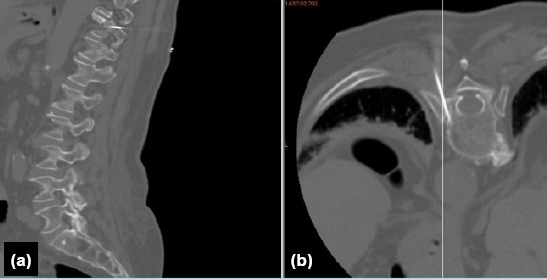

Methods: Fourteen patients undergoing posterior aproach to the thoracic spine and/or spinal cord related lesions were investigated. Spinocaths were placed under CT guidance, into the pedicle of the relevant vertebra, at the same day or the night before surgery. The surgical field is prepared as usual, and a spinocath is placed to the relevant thoracic pedicle under CT guidance.

Results: Intraoperative level localization was more reliable and easier in patients undergoing preoperative CT-guided marking in surgeries on the thoracic region performed for various reasons. Shorter preoperative preparation and intraoperative anesthesia times, a decrease in number of fluoroscopic images taken intraoperatively, and no spinal mislocalizations were observed.

Conclusion: The results obtained suggest that localising the level with preoperative CT before all types of thoracic surgery is a safe, reliable, and useful method for thoracic spine surgery.